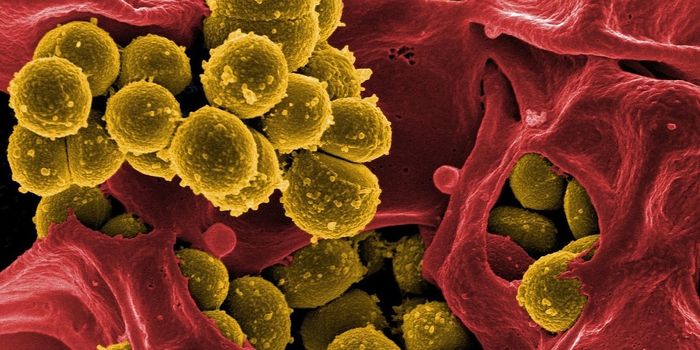

SEP 17, 2021Cell & Molecular BiologyMRSA (methicillin-resistant Staphylococcus aureus) is a well known superbug, a pathogenic microbe that can cause serious ...